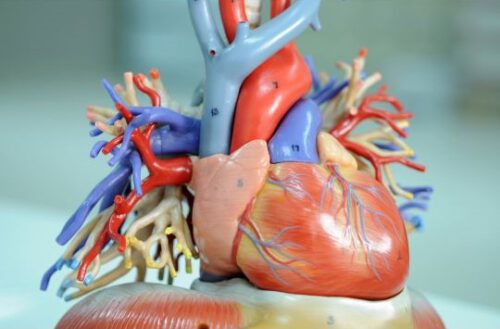

Das menschliche Herz ist ein komplex aufgebautes Hohlorgan. Als eine Art Pumpstation sorgt es durch den Herzschlag für den notwendigen Blutfluss und die Blutversorgung des Körpers. So werden Organe und Gewebe mit Blut und gleichzeitig mit lebenswichtigem Sauerstoff und Nährstoffen versorgt. Im Ruhezustand schlägt das Herz eines Erwachsenen ca. 60- bis 80-mal pro Minute, umgerechnet ca. 100.000 Mal pro Tag und befördert bei jedem Herzschlag Blut durch den Körper. Insgesamt werden ca. 5 Liter Blut pro Minute durch den Körper gepumpt. Das menschliche Herz ist etwa faustgroß, innen hohl und wiegt zwischen 250 g (bei Frauen) und 300 g (bei Männern).

Das Herz besteht aus Herzkammern sowie auch -klappen und einem verzweigten System aus Venen und Arterien. Eine Scheidenwand, genannt Septum, trennt das Organ in zwei Hälften. Jede Hälfte besteht aus zwei Hohlräumen, dem Vorhof und der Herzkammer. Die beiden Hälften sind ähnlich aufgebaut, sie erfüllen jedoch unterschiedliche Aufgaben. Der linke Teil versorgt die Organe mit sauerstoffreichem Blut und der rechte Teil empfängt über die obere Hohlvene sauerstoffarmes Blut und leitet es weiter in den Lungenkreislauf. Das Blut wird in der Lunge wieder mit Sauerstoff angereichert und fließt von dort aus zurück in den Vorhof der linken Herzhälfte – damit schließt sich der Blutkreislauf.

Das Blut fließt immer in dieselbe Richtung. Damit das sichergestellt ist, verfügt das Herz über vier Herzklappen, jeweils eine zwischen Vorhof und Kammer in jeder Herzhälfte sowie zwei Herzklappen an den beiden Ausgängen der Schlagadern. Die Herzklappen sorgen, wie Ventile dafür, dass das Blut nicht zurückströmt. Ein Teil des Blutes fließt in die Herzkranzgefäße, auch Koronararterien genannt (befinden sich rund um das Herz) und versorgt das Herz selbst mit sauerstoffreichem Blut. Durch Ablagerungen in den Gefäßen können sich Koronararterien verengen. Verschließt sich ein Herzkranzgefäß, dann kommt es zu einem Herzinfarkt.